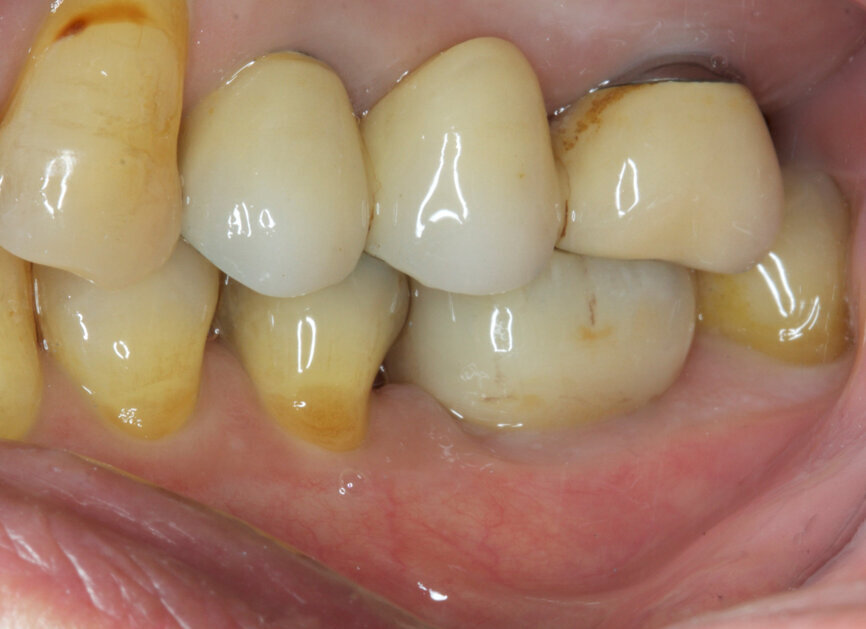

Fig. 24: Final result—lateral view.

Fig. 25: Final result—occlusal view.

Fig. 26: Final outcome radiograph.

Fig. 27: Straumann TLX one-year follow-up clinical outcome.

Fig. 28: Straumann TLX one-year follow-up clinical outcome.

Fig. 29: One-year follow-up radiograph showed peri-implant stability.

From a clinical perspective, the immediate placement and function were very well indicated as they could be verified through the gingival margins and health, and bone levels throughout the healing phase, and final and one-year follow-up images (Figs. 24–29).